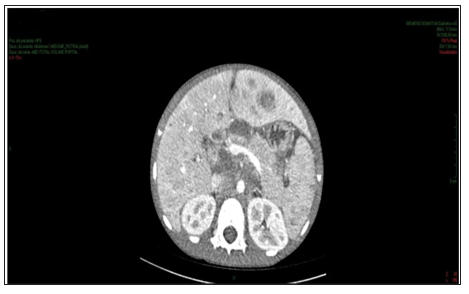

Figure 1: Contrast-enhanced abdomen CT showing increased dimensions of the liver with heterogeneous density at the expense of diffuse hypodense images. Spleen enlarged and heterogeneous.

Enhanced abdominal CT performed on the 1st day of hospitalization, revealed enlarged liver, with heterogeneous attenuation, at the expense of diffuse, ill-defined, sparse hypodense images, measuring up to 2.4 cm in segment II. Mild dilation of the intrahepatic bile ducts. Spleen enlarged, heterogeneous texture, at the expense of diffuse hypodense images. A hypodense, amorphous, poorly delimited (Figure 1). Expansive formation located in retroperitoneum and mesenteric root with involvement of the mesenteric vessels, without determining stenosis of the same, consistent with lymph node conglomerate. Prominent para-aortic lymph nodes, measuring up to 2.6 x 1.4 cm (Figure 2). Moderate amount of free fluid in the abdominal cavity. Hypodense and hypocaptant mass of ill-defined limits on the right flank, compatible with lymph node mass (Figure 3). In chest CT no lymph node enlargement was been in the mediastinum. On the 3rd day of hospitalization, abdominal ultrasonography was also performed to corroborate the CT findings, evidencing an enlarged liver, diffusely heterogeneous with small hypoechoic solid nodules distributed in the hepatic parenchyma. Heterogeneous pancreas, with presence of solid hypoechoic nodule, adjacent to the body, measuring 2.3 cm, suggesting lifonodomegaly. Enlarged spleen with presence of multiple hypoechoic solid nodules of small dimensions. Moderate ascites. Solid mass on the right flank measuring approximately 10 cm suggestive of confluent lymph nodes. The left inguinal lymph node biopsy was analyzed by the simple “imprint” and “cell block”, the macroscopy of which describes a brownish, lobed and unctuous fragment measuring 1.3 x 0.6 x 0.4 cm. Microscopy showed a chronic/acute granulomatous inflammatory process containing multinucleated giant cells in the lymph node tissue. Special coloring by the PAS and Grocott method evidenced fungal structures suspected of Paracoccidioides (Figures 4 & 5).